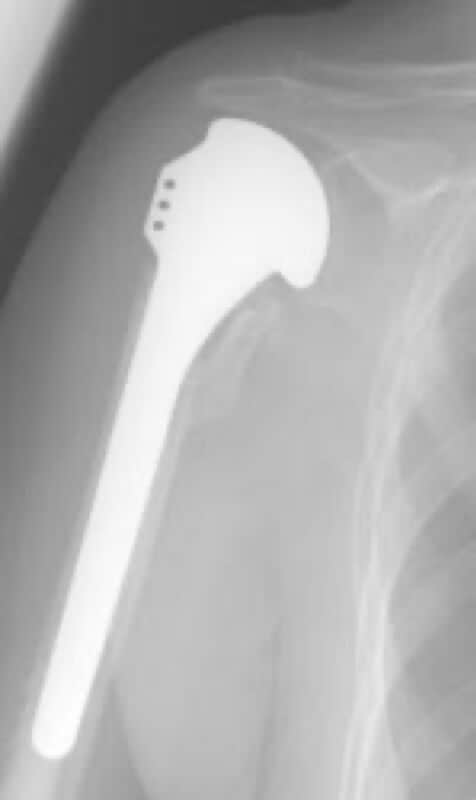

DePuy, HRP